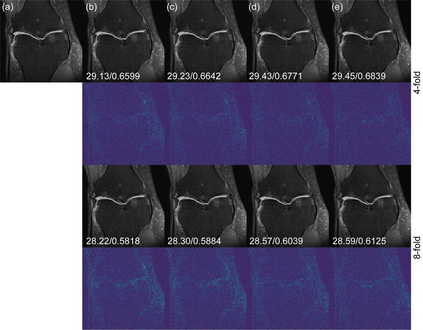

Deep learning-based MRI reconstruction models have achieved superior performance these days. Most recently, diffusion models have shown remarkable performance in image generation, in-painting, super-resolution, image editing and more. As a generalized diffusion model, cold diffusion further broadens the scope and considers models built around arbitrary image transformations such as blurring, down-sampling, etc. In this paper, we propose a k-space cold diffusion model that performs image degradation and restoration in k-space without the need for Gaussian noise. We provide comparisons with multiple deep learning-based MRI reconstruction models and perform tests on a well-known large open-source MRI dataset. Our results show that this novel way of performing degradation can generate high-quality reconstruction images for accelerated MRI.